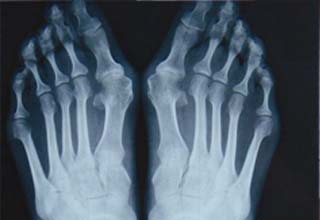

拇指外翻作为一种疾病,虽然早期除了外观不美丽、选鞋困难及容易损坏鞋形,还没有给人们带来太多的不适症状。但是随着年龄增长,拇外翻畸形程度的加重,会产生很多严重的并发症,如拇囊炎肿、爪形趾、鸡眼、脚垫等;这些并发症的发生不仅影响足部功能,而且会产生疼痛,严重影响生活和工作。所以,建议当发现有拇外翻畸形时,好及早防治,这样,不仅能够延缓拇外翻恶化的程度,并且可以有效地预防一些并发症的发生。>>>点击了解拇外翻的病因,以了解更多的预防方法

2、拇外翻微创矫形术,手术前通过X片有效确定截骨位置和角度,创面只需3-5mm微孔,完成截骨矫形,骨凸去平、手法复位。外翻、内翻同时矫正。由于跖骨的内稳定作用,术后即可简易行走,2周后鼓励活动,一个月临床愈合,恢复活动。>>>生活中有哪些方法能有效预防拇外翻的发生?点击了解